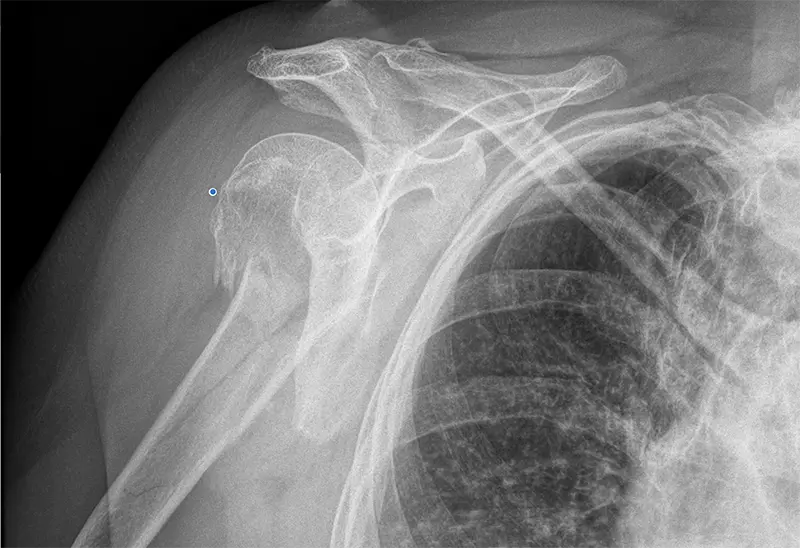

Osteosynteza to operacja mająca na celu zmniejszenie i ustabilizowanie złamanych fragmentów kości, zwłaszcza w przypadku złamań kości ramiennej. Zabieg ten polega na zespoleniu różnych fragmentów kości w jak najbardziej anatomicznej pozycji, co ma na celu przywrócenie integralności struktury kostnej oraz przywrócenie prawidłowej funkcji stawu ramiennego.

W przypadku złamań górnej części kości ramiennej, istnieje kilka technik, które można zastosować. Mogą to być szpilki, płytki ze śrubami, same śruby lub gwoździe (metalowe pręty). Istnieje również możliwość rekonstrukcji guzowatości kości, co jest szczególnie ważne w przypadku naprawy ścięgna mankietu rotatorów.